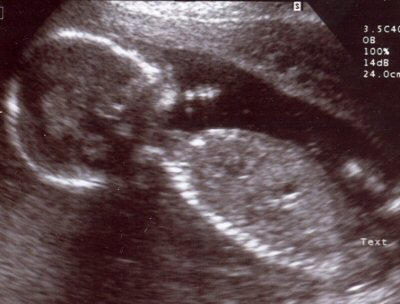

Above is a hospital sonogram image of a human child in its mother's womb soon to be born.

The day for the annual March For Life in

Washington, DC dawned both very cold and cloudy. Cold,

perhaps, because on this exact day in the winter of 1973 that

the United States Supreme Court announced its Roe v Wade

decision but did not examine the scientific evidence that the

yet unborn child carried by its mother was a human. The